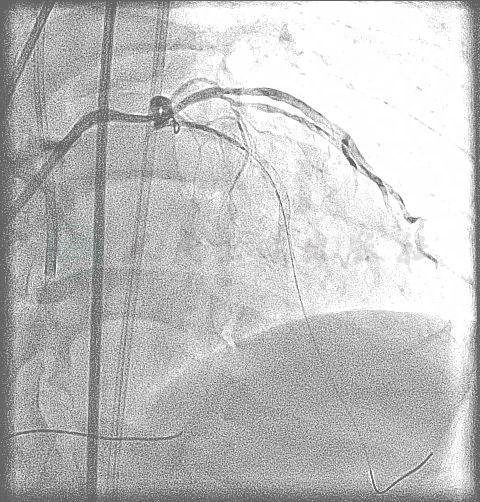

冠状动脉造影:左主干血管粗大,体部及远段50%左右狭窄;左前降支根部闭塞;左回旋支中等大小,轻度动脉硬化,未见明显狭窄,远段血流TIMI 3级;中间支粗大,其中一个分支呈现中重度狭窄。右冠状动脉优势型,近中段50%左右弥漫性狭窄,PDA近段50%左右管状狭窄,远段血流TIMI 3级,可见良好的侧支循环逆向充盈LAD中远段的血管(图2~图8)。左心室造影显示左心室功能良好(图9)。

图2 冠状动脉造影(LAO 43°),显示右冠状动脉呈现弥漫性动脉硬化,近中段和后降支近段50%左右的狭窄,远段血流TIMI 3级

图3 冠状动脉造影(Cran 20°),显示右冠状动脉弥漫性动脉硬化,近中段和后降支近段50%左右的狭窄,远段血流TIMI 3级